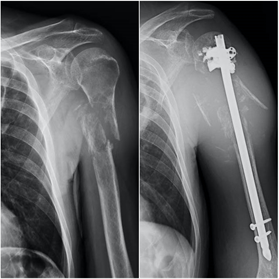

Es una lesión ósea frecuente en la infancia y es con diferencia la fractura patológica más frecuente en los niños que presentan una lesión ósea. La localización más frecuente es en el húmero proximal, seguido del fémur proximal. Las imágenes radiológicas mostrarán una fractura o una fisuración de la cortical del huso sobre una lesión radiolucente redondeada con o sin expansión de las corticales. El tratamiento habitual suele precisar únicamente la inmovilización ortopédica con yeso pues la consolidación correcta de la fractura es frecuente. En las fracturas desplazadas o en la extremidad inferior puede ser necesaria la cirugía.

Los sarcomas óseos son tumores óseos muy infrecuentes, con una incidencia aproximada de 1 caso por cada 100.0000 habitantes. El Osteosarcoma es el tumor óseo primario maligno más frecuente en la infancia, seguido por el el Sarcoma de Ewing. En las radiografías se suelen evidenciar lesiones líticas, permeativas, con destrucción ósea, reacción perióstica y afectación del los tejidos blandos cercanos. Estos pacientes ,además de dos proyecciones radiográficas, precisarán estudios complementarios de imagen, biopsia, estudio de extensión para descartar diseminación pulmonar, y valoración multidisciplinar. La cirugía oncológica de salvamento de extremidad y reconstrucción es la técnica de elección.

El fémur es la localización principal, con predominio de la zona de la cadera. Otras localizaciones son la columna vertebral, la pelvis, los huesos planos y el húmero. En la espalda el dolor suele estar presente antes que los cambios radiográficos, mientras que cuando el dolor se localiza en los huesos largos suelen ya existir lesiones con riesgo de fractura.

En el cáncer diseminado el tratamiento de las metástasis suele ser paliativo, mediante estabilización de la fractura con osteosíntesis o implante de prótesis. En ocasiones la osteosíntesis se suplementa con aporte de cementos biológicos para aumentar la estabilidad o se realiza radioterapia complementaria. En casos de metástasis únicas, el tratamiento quirúrgico radical de la metástasis puede estar indicado, lo que hace necesaria la valoración conjunta de traumatología oncológica y oncología médica ante la detección de una lesión metastásica ósea en nuestra práctica.